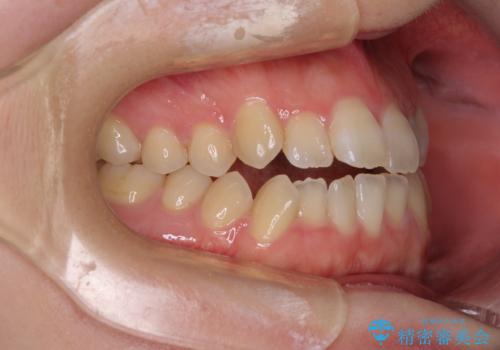

オープンバイトと前歯のデコボコをインビザライン矯正で解消

- 前歯の開咬を気にして来院された患者様です。

開咬の治療は、前歯を閉じるように動かすとともに、上下臼歯を圧下(骨内にめり込ませる)させることで進めて行きます。

インビザラインは臼歯の圧下を効果的に行えるため、インビザラインを用いて矯正治療を行うこととしました。